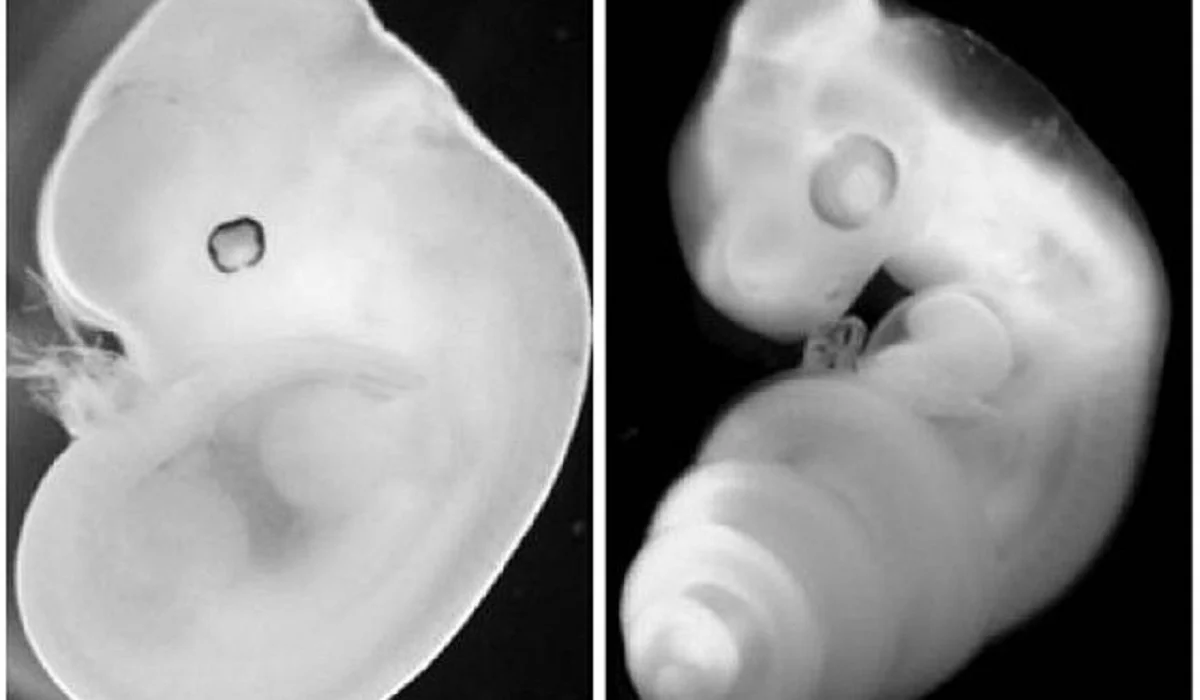

Με μια πρωτοποριακή μέθοδο που παρέκαμψε την ανάγκη να προϋπάρχει σπέρμα, ωάρια και γονιμοποίηση, επιστήμονες δημιούργησαν τα πρώτα «συνθετικά έμβρυα» στον κόσμο

Πιο συγκεκριμένα, οι ερευνητές από το Ινστιτούτο Weizmann στο Ισραήλ ανακάλυψαν ότι τα βλαστοκύτταρα από ποντίκια θα μπορούσαν να κατασκευαστούν με τέτοιο τρόπο ώστε να αυτοσυναρμολογηθούν σε πρώιμες δομές που μοιάζουν με έμβρυο το οποίο διαθέτει εντερικό σωλήνα, έναν πρώιμο εγκέφαλο και μια καρδιά που χτυπά.

Γνωστά ως «συνθετικά έμβρυα» επειδή δημιουργούνται χωρίς γονιμοποιημένα ωάρια, οι δομές αυτές αναμένεται να οδηγήσουν σε βαθύτερη κατανόηση του πώς σχηματίζονται τα όργανα και οι ιστοί κατά την ανάπτυξη των φυσικών εμβρύων.

Πέρυσι, η ίδια επιστημονική ομάδα ανακοίνωσε τη δημιουργία μιας μηχανικής μήτρας που επέτρεπε σε φυσικά έμβρυα ποντικών να αναπτυχθούν. Στην πιο πρόσφατη μελέτη, η ίδια συσκευή χρησιμοποιήθηκε για την ανατροφή των βλαστοκυττάρων ποντικιού για περισσότερο από μια εβδομάδα.

Αν και τα περισσότερα από τα βλαστοκύτταρα απέτυχαν να σχηματίσουν δομές που μοιάζουν με έμβρυο, περίπου στο 0,5% αναπτύχθηκαν ιστοί και όργανα.

Σε σύγκριση με φυσικά έμβρυα ποντικού, τα συνθετικά έμβρυα ήταν κατά 95% όμοια όσον αφορά την εσωτερική τους δομή και τα γενετικά προφίλ των κυττάρων. Σύμφωνα με τους επιστήμονες, τα όργανα που σχηματίστηκαν ήταν λειτουργικά. Ο Τζέικομπ Χάνα ανέφερε βέβαια ότι τα συνθετικά έμβρυα δεν είναι «πραγματικά» έμβρυα και δεν είχαν τη δυνατότητα να εξελιχθούν σε ζωντανά ζώα.